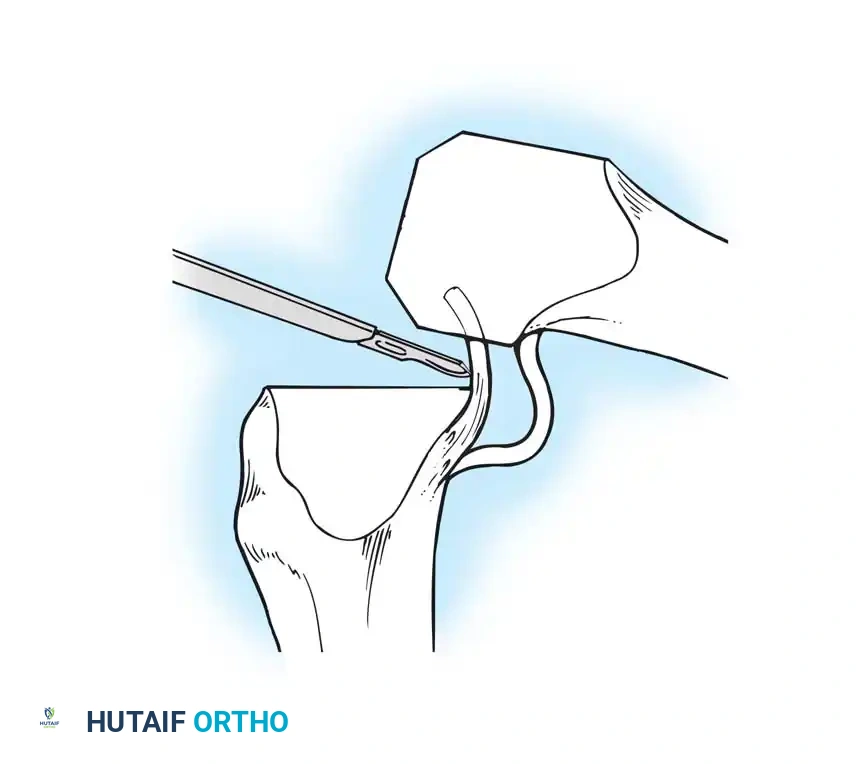

⚠️ Surgical Warning: Patellar Tendon Avulsion

During all maneuvers that place tension on the extensor mechanism—especially knee flexion and patellar retraction—pay careful attention to the patellar tendon attachment at the tibial tubercle. Avulsion of the patellar tendon is a devastating complication that is notoriously difficult to repair.

- With both PCL-substituting and PCL-retaining procedures, subluxate and externally rotate the tibia. External rotation relaxes the extensor mechanism, decreases the risk of patellar tendon avulsion, and dramatically improves exposure of the lateral compartment.